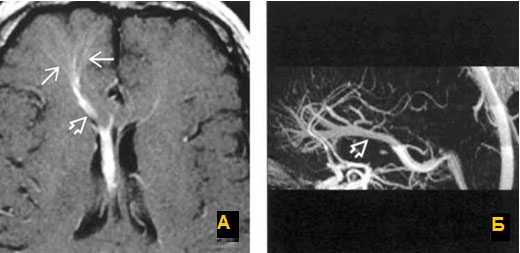

А: на МР-ангиограмме в латеральной проекции отмечается окклюзия верхнего сагиттального синуса вследствие опухолевой инвазии.

В: МРТ-реконструкция изображения визуализирует окклюзию сагиттального венозного синуса и объемный характер опухоли.

Тромбоз правого поперечного синуса - гипоинтенсивные участки по Т2 (внутриклеточный дезоксигемоглобин).

МРТ головного мозга: справа (зеленая стрелка) на Т2-взвешенном изображении отмечается имеющийся в норме феномен «пустоты потока» от правого сигмовидного синуса и яремной Вены. Слева (оранжевая стрелка) отмечается аномально высокий сигнал, в результате, вероятнее, тромбоза. Для подтверждения синус-тромбоза и окончательного определения локализации и протяженности тромбоза необходимо проведение МР-венографии.